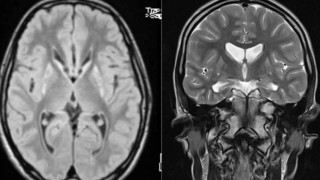

Πρωτοποριακή θεραπεία για τη νόσο του Χάντινγκτον επιβραδύνει την εξέλιξη της ασθένειας κατά 75% Metrosport Team 25.09.2025